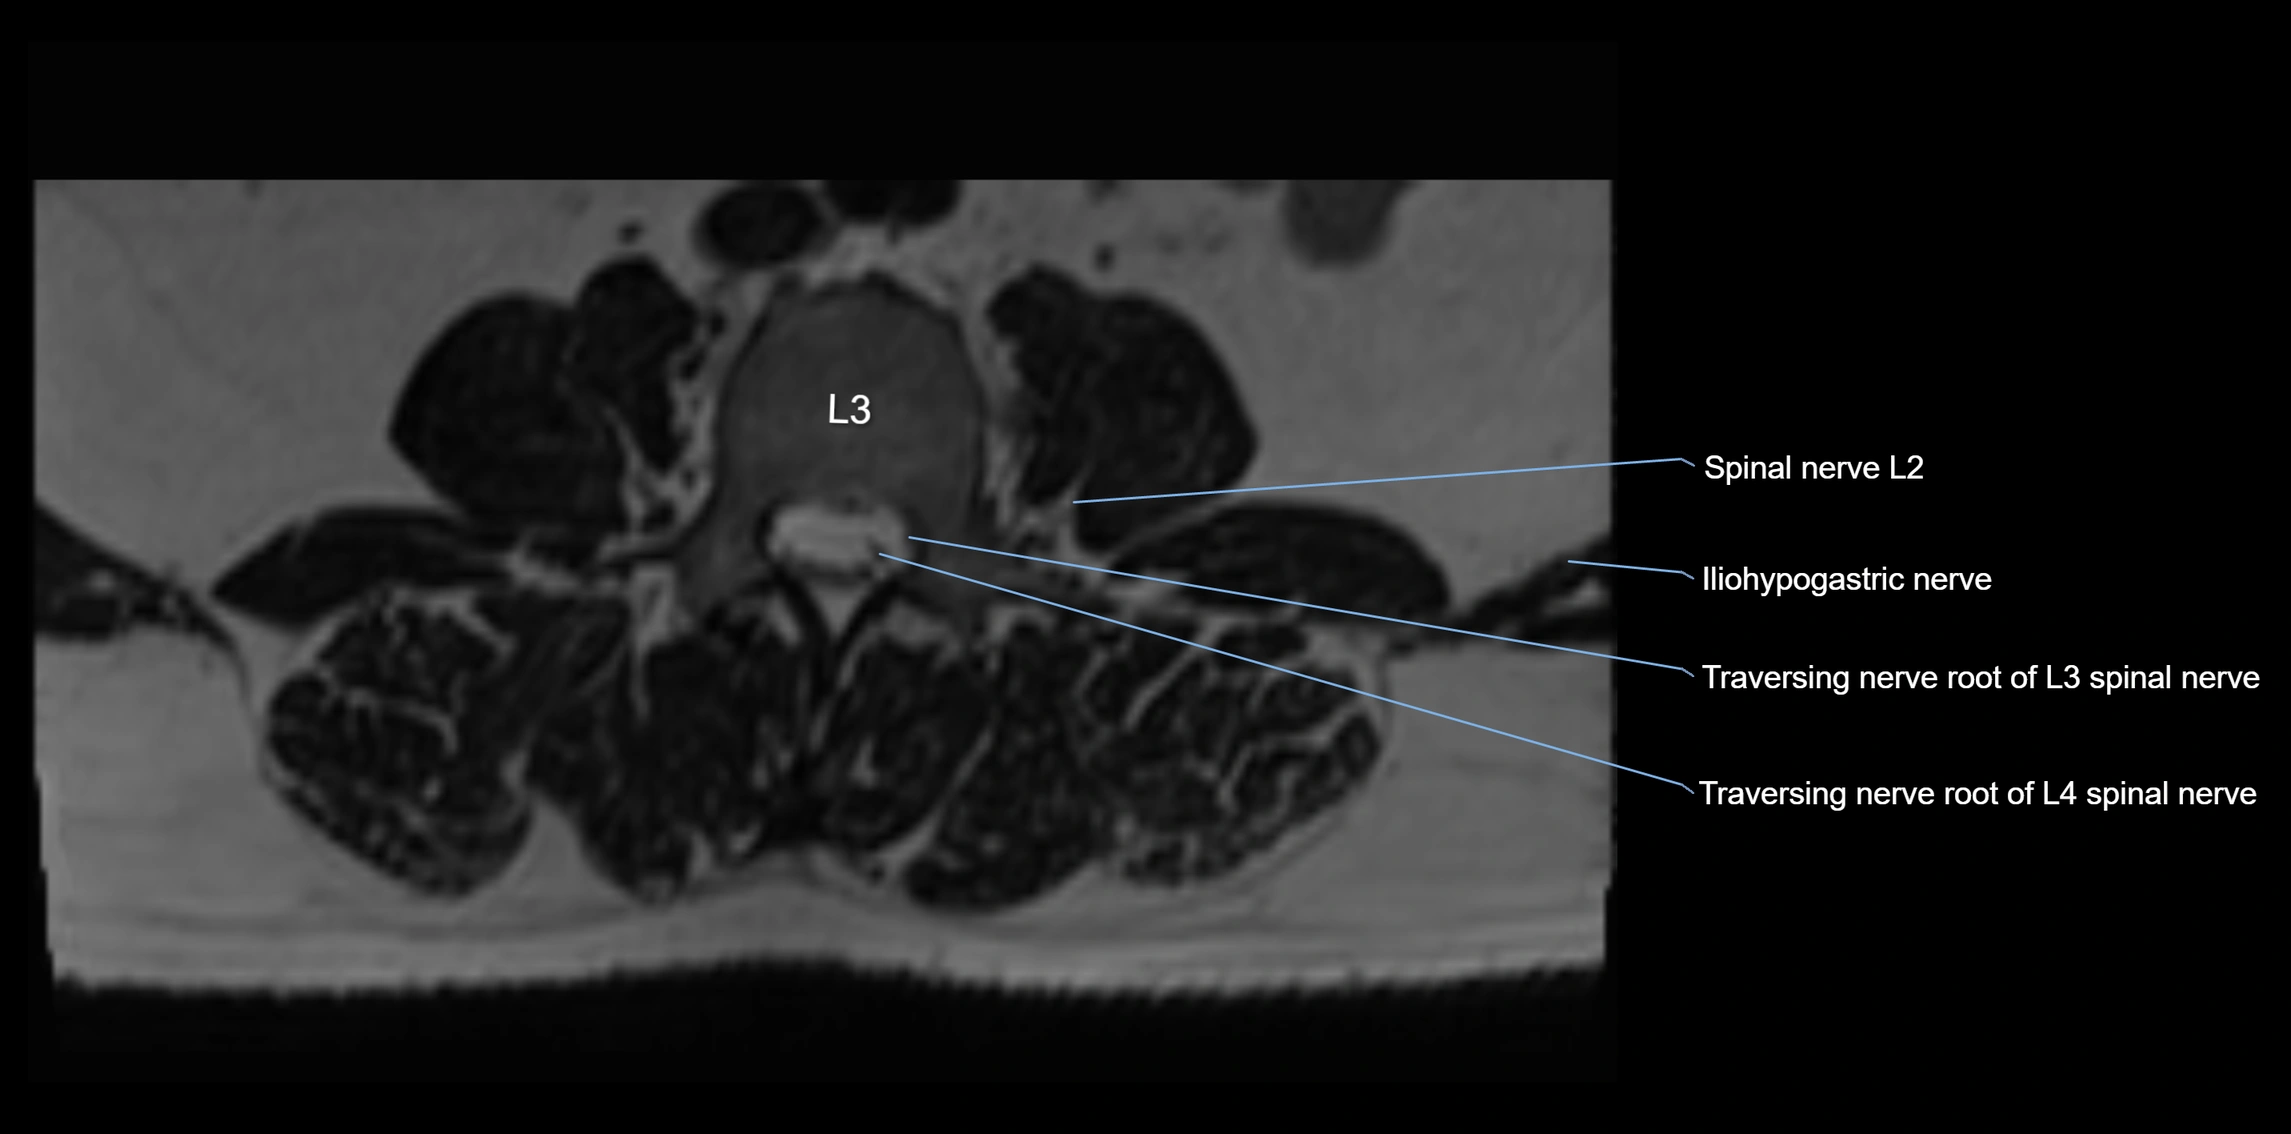

MRI image

image